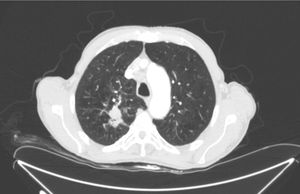

Foram feitas duas biópsias por punção e um novo exame de sangue, inclusive níveis séricos de proteína, sorologias virais, esfregaço de sangue, enzimas musculares, células de Sézary, citometria de fluxo e marcadores imunológicos e tumorais. Os demais achados laboratoriais estavam dentro dos limites normais (inclusive aldolase sérica), exceto CPK (1,309 UI/L; valores de referência: 1 a 175 UI/L) e CK‐MB (27,3 UI/L; valores de referência: 0 a 20 UI/L). Os exames histopatológicos revelaram discretas alterações espongióticas e psoriasiformes com hiperceratos folicular discreta, bem como características histopatológicas inespecíficas (fig. 4). Foi iniciado um tratamento de suporte com ênfase em dieta hiperproteica, controle de temperatura e hidratação, além de administração de esteroides tópicos. Devido à nova perda de peso e à preocupação quanto a uma neoplasia maligna subjacente como causa potencial da eritrodermia, foi feita uma avaliação completa para doença maligna oculta. A tomografia computadorizada de tórax revelou lesão nodular de 22×34mm no lobo superior direito com múltiplas linfadenopatias (fig. 5), a histopatologia era compatível com carcinoma epidermoide. A tomografia computadorizada da cabeça evidenciou duas lesões metastáticas occipitais, foram finalmente classificadas como estágio IV (T2N3M1). Às seis semanas, a erupção cutânea do paciente era similar à da apresentação inicial, porém com menos prurido. O paciente faleceu três meses após o diagnóstico devido à progressão do câncer metastático.